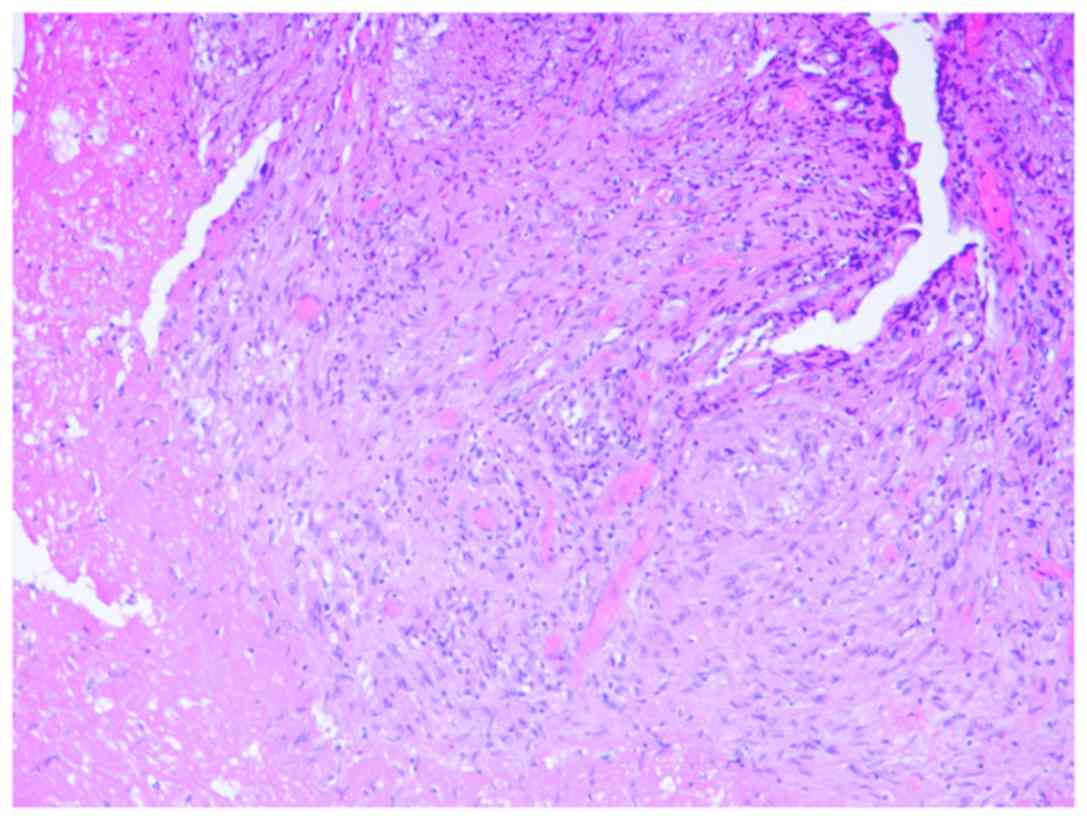

Tissue samples were fixed in 10% neutral formalin for 8–48 h, dehydrated by 75, 95 and 100% ethanol, embedded in paraffin and sliced into 4-µm-thick sections. The samples were stained with hematoxylin for 5–10 min and eosin for 1–3 min at the room temperature. The sections were observed using an optical microscope at a magnification of ×300. Histopathological examination with hematoxylin and eosin revealed an inflammatory reaction, including massive granuloma with central necrosis, lymphocytic infiltration, and a small amount of neutrophil infiltration (Fig. 3). Bacterial and fungal cultures provided negative results after culturing for 2 weeks.

Figure 3.

Histopathological examination with hematoxylin and eosin revealing an inflammatory reaction, including a massive granuloma with central necrosis, lymphocytic infiltration and a small amount of neutrophil infiltration. Magnification, ×200.